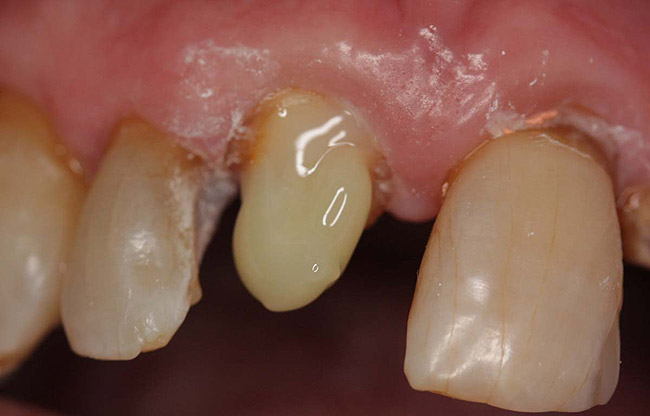

Case 1

A Class IN maxillary bicuspid was previously restored with a fiber post and an all-porcelain crown (Figure 1). The forces of the oral environment resulted in fracture of the fiber post and crown failure. The remaining fiber post in the root was removed, and anti-rotational areas were prepared for a cast post (Figure 2). A gold cast post was constructed at a dental laboratory, using an indirect technique (Figure 3). A porcelain-fused-to-metal (PFM) crown was constructed with a bevel finish to provide a ferrule and reduce forces on the post (Figure 4 and Figure 5).

Figure 2  Same second bicuspid as Figure 1 after removal of the fractured fiber post.

Figure 2